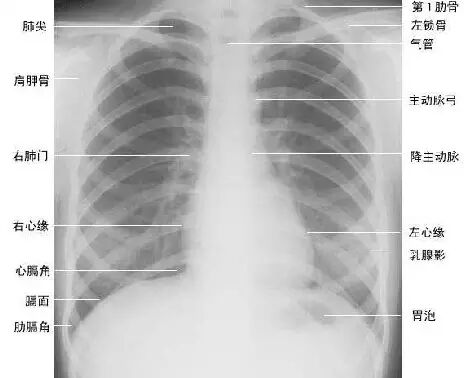

下面为大家依次介绍胸部正常X线解剖

1.肺叶段X线解剖

肺叶

右肺:由水平裂和斜裂分为上、中、下三叶

肺:由斜裂分为上、下两叶

斜裂:起自第5胸椎水平,倾斜向前下,大致与第6肋骨平行,止于前胸膜沟(前肋膈窦)后方数厘米的膈肌处。

水平裂:大致呈水平走形,与第4前肋大致同水平,前部常低于后部,外侧部常低于内侧部。

2.肺纹理

肺纹理为自肺门向肺野呈放射状分布的树枝状阴影,它主要是肺动脉的投影,肺静脉、支气管和淋巴管也参与形成。肺纹理由肺门向外围延伸,逐渐变细,至肺野外带渐细小而稀少,距侧胸壁内缘约1cm范围内的肺野基本无肺纹理可见(图下图)。

3.肺野、肺带的划分

纵隔两旁含气的肺在胸片上所显示的透明区域称肺野,其透明度随呼吸而改变,深吸气时肺内含气量增多,透明度增高,呼气时则相反。

为便于指明病变的部位,通常人为地将一侧肺野纵向分为三等分,即内、中、外带。分别在两侧第2、4肋骨前端下缘划一水平线,将肺野横向分为上、中、下三个肺野。(如上图)。